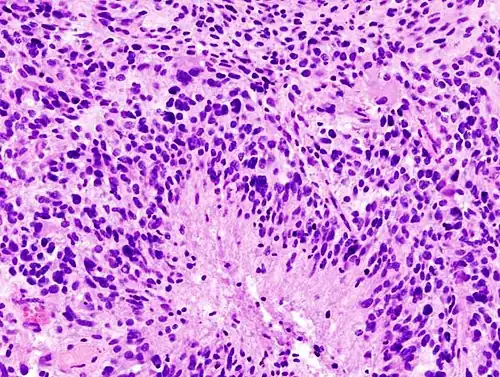

Brain tumor classification has been traditionally based on histopathology at macroscopic level, measured in hematoxylin-eosin sections. The World Health Organization published the first standard classification in 1979[34] and has been doing so since. The 2007 WHO Classification of Tumors of the Central Nervous System[35] was the last classification mainly based on microscopy features. The new 2016 WHO Classification of Tumors of the Central Nervous System[36] was a paradigm shift: some of the tumors were defined also by their genetic composition as well as their cell morphology.

When viewed with MRI, glioblastomas often appear as ring-enhancing lesions. The appearance is not specific, however, as other lesions such as abscess, metastasis, tumefactive multiple sclerosis, and other entities may have a similar appearance.[61] Definitive diagnosis of a suspected GBM on CT or MRI requires a stereotactic biopsy or a craniotomy with tumor resection and pathologic confirmation. Because the tumor grade is based upon the most malignant portion of the tumor, biopsy or subtotal tumor resection can result in undergrading of the lesion. Imaging of tumor blood flow using perfusion MRI and measuring tumor metabolite concentration with MR spectroscopy may add diagnostic value to standard MRI in select cases by showing increased relative cerebral blood volume and increased choline peak, respectively, but pathology remains the gold standard for diagnosis and molecular characterization.

Distinguishing glioblastoma from high-grade astrocytoma is important. These tumors occur spontaneously (de novo) and have not progressed from a lower-grade glioma, as in high-grade astrocytomas.[6] Glioblastomas have a worse prognosis and different tumor biology, and may have a different response to therapy, which makes this a critical evaluation to determine patient prognosis and therapy.[45][62] Astrocytomas carry a mutation in IDH1 or IDH2, whereas this mutation is not present in glioblastoma. Thus, IDH1 and IDH2 mutations are a useful tool to distinguish glioblastomas from astrocytomas, since histopathologically they are similar and the distinction without molecular biomarkers is unreliable.[46] IDH-wildtype glioblastomas usually have lower OLIG2 expression compared with IDH-mutant lower grade astrocytomas.[63] In patients aged over 55 years with a histologically typical glioblastoma, without a pre-existing lower grade glioma, with a non-midline tumor location and with retained nuclear ATRX expression, immunohistochemical negativity for IDH1 R132H suffices for the classification as IDH-wild-type glioblastoma.[60] In all other instances of diffuse gliomas, a lack of IDH1 R132H immunopositivity should be followed by IDH1 and IDH2 DNA sequencing to detect or exclude the presence of non-canonical mutations.[60] IDH-wild-type diffuse astrocytic gliomas without microvascular proliferation or necrosis should be tested for EGFR amplification, TERT promoter mutation and a +7/–10 cytogenetic signature as molecular characteristics of IDH-wild-type glioblastomas.[60]